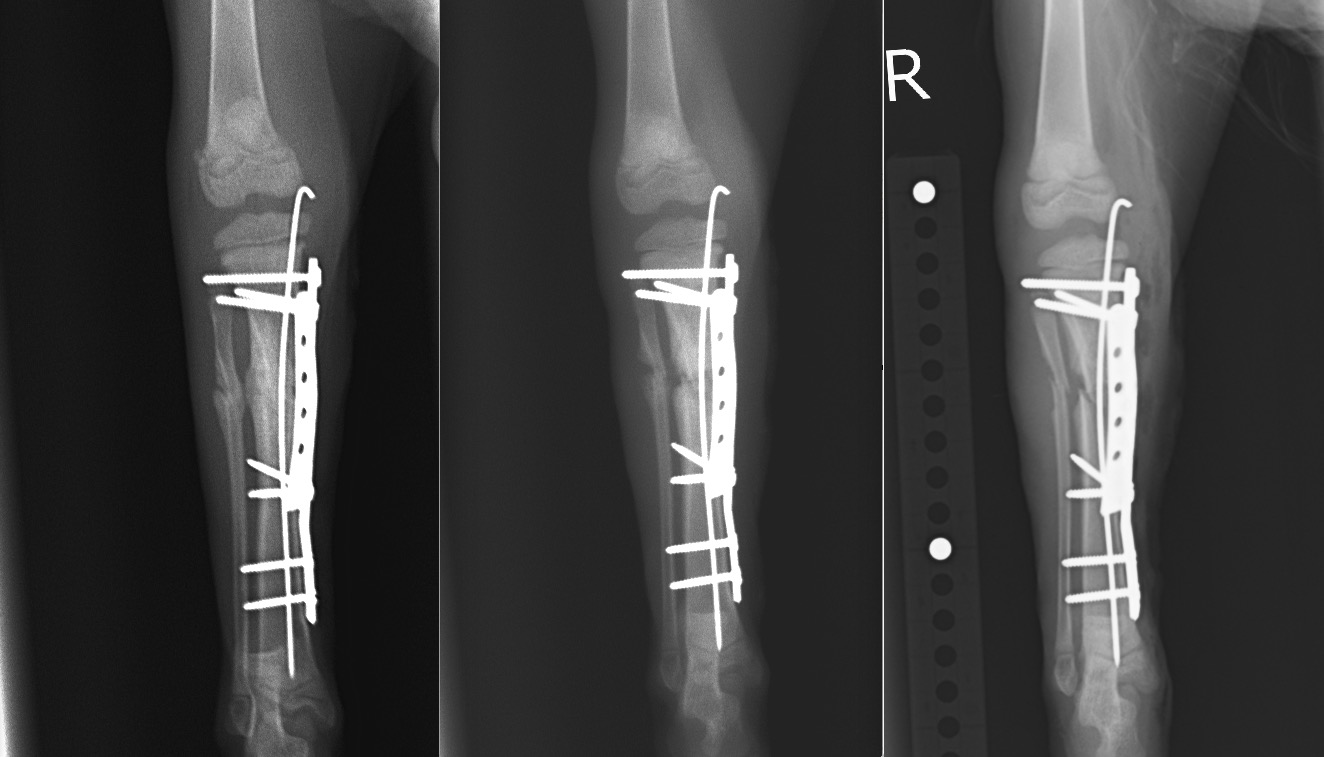

術直後、2週間後、4週間後のX線写真です。

若いゆえに治癒も早く、2週間でかなり骨の癒合が進み、4週間で骨折がほとんど治ってしまっています。

術後4週間/術後2週間/術直後